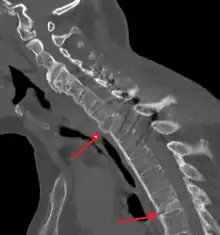

The earliest changes demonstrable by plain x–ray shows erosions and sclerosis in sacroiliac joints. Progression of the erosions leads to widening of the joint space and bony sclerosis. X-ray spine can reveal squaring of vertebrae with bony spur formation called syndesmophyte. This causes the bamboo spine appearance. A drawback of X-ray diagnosis is the signs and symptoms of AS have usually been established as long as 7–10 years prior to X-ray-evident changes occurring on a plain film X-ray, which means a delay of as long as 10 years before adequate therapies can be introduced.[19]

Options for earlier diagnosis are tomography and MRI of the sacroiliac joints, but the reliability of these tests is still unclear.

Lateral X-ray of the neck in ankylosing spondylitisImaging

CT scan showing bamboo spine in ankylosing spondylitis